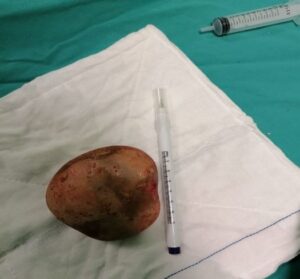

Ordu’nun Fatsa ilçesinde idrar yolu enfeksiyonu bulunan hastanın mesanesinden büyük boy patates yumrusu kadar taş çıkarıldı.

Sürekli idrar yolu enfeksiyonu olan ve dayanılmaz idrar yanması, sık idrara çıkma ve idrar tutmakta zorlanması olan hasta ilaç tedavilerinden fayda görmemesi üzerine Fatsa Devlet Hastanesi Üroloji Polikliniği de Opr. Dr Yüksel Şahin’e başvurdu. Yapılan tetkik ve tahliller sonucunda hastanın mesanesinde çok büyük bir taş saptandı.

Literatürde bu boyda taş görülmesi çok nadir karşılanırken hastanın mesanesinden çıkan taş şaşkınlıkla karşılandı. Derhal ameliyata alınan hastanın mesanesindeki taş kapalı yöntemle çıkarılması mümkün olmadığından açık sistolitotomi ameliyatı yapıldı. Herkesi şaşkına çeviren büyük bir patates yumrusu şeklindeki taş başarılı şekilde alındı.iha